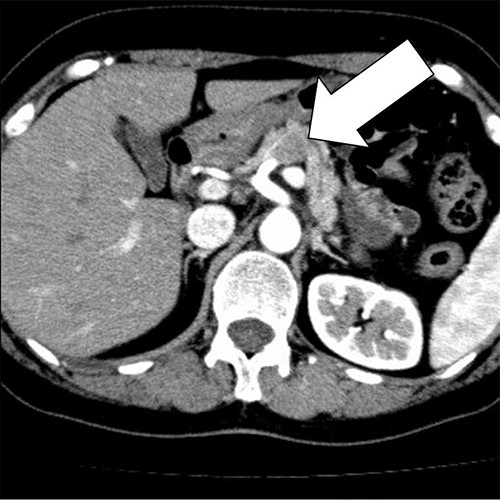

Histologically, the main lesion of the tumor showed proliferation of atypical mucin-producing columnar epithelial cells lining follicle-like or cystically dilated tubular structures representing well-differentiated adenocarcinoma. The diffuse proliferation of atypical short spindle cells and round cells accompanied by multinucleated giant cells aggregation was observed around the tubular structure. The giant cells had multiple small round nuclei, which gather in the centrocytic portion, resembling OCGCs (Fig. 4).

The diffuse proliferation of atypical short spindle cells and round cells accompanied by multinucleated giant cells aggregation was observed around the tubular structure. The giant cells had multiple small round nuclei which gather in the centrocytic portion, resembling OCGCs.